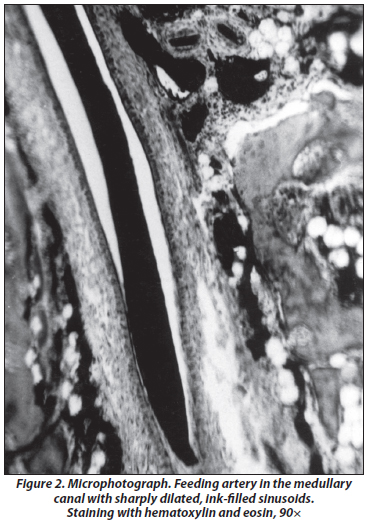

Focal bone marrow avascularity is noted. In the proximal part of the medullary cavity there are large dilated branches of the feeding artery filled with carcasses (Fig. 2). Bone marrow with sharply dilated sinusoids and multiple cysts. Avascularity of the end of the cortical diaphyseal layer over 1–2 cm is observed (Fig. 3). Above this zone, there is enlargement of a part of Haversian and Volkmann’s canals. The absence of cellular elements is noted in many of them. Impoverishment and irregularity of vascular network. The capillaries are located near the wall in connection with perivascular edema (Fig. 4).

/54_2.jpg)